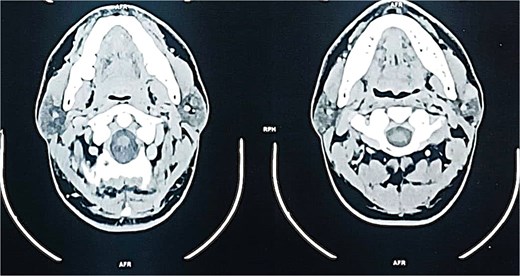

A contrast-enhanced computed tomography (CT) scan of the neck revealed a well-circumscribed, oval lesion located within the superficial lobe of the left parotid gland. The mass measured 20 × 16 × 14 mm, appeared isodense and homogeneous on pre-contrast images, and showed intense enhancement after contrast injection, consistent with a solid, vascular lesion (Figs. 2 and 3).

Coronal contrast-enhanced CT scan confirming the presence of an oval, homogeneous, enhancing lesion in the left parotid gland.